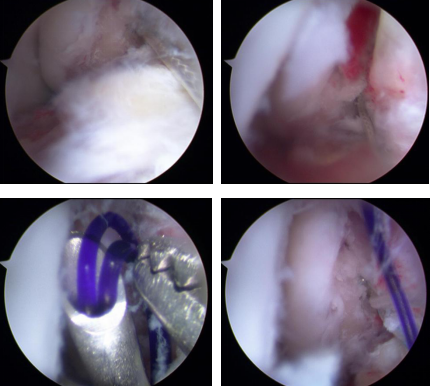

关节镜下清理

距骨骨折进行手术治疗有一个比较棘手的并发症,就是骨折不愈合和距骨缺血性坏死,治疗中精准的复位固定和尽可能地减少对距骨血供的伤害是关键。讨论后,石荣剑副院长曹广超主任团队决定利用踝关节镜联合机器人治疗距骨骨折。术中,进行关节镜下探查清理,克氏针撬拨复位骨折端;打入克氏针固定骨折端,再在机器人的精准辅助下打入导针,拧入螺钉。手术仅数个0.5厘米切口,创口微乎其微,患者非常满意。